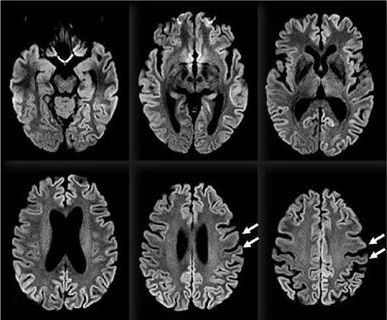

It is most common prion disease but a very rare form of dementia. CJD is among transmissible spongiform encephalopathies, all of which is characterised by spongy degeneration, neuronal loss and astrocytic proliferation. In CJD an abnormal protease resistant prion protein accumulates in brain. It causes subacute dementia with ataxia and myoclonic jerks. New variant CJD (mad cow disease) is more slowly progressing seen in younger adults after eating contaminated beef. CJD's rapid progression and presence of myoclonus distinguish it from other dementias. Diagnosis is suggested by clinicak features. Increased levels of CSF and tau proteins indicate rapid destruction of brain neurons. MRI and EEG may be helpful. Specimens should be handled with precaution to prevent transmission. There is currently no effective treatment. Patients die within 1 year of transmission.